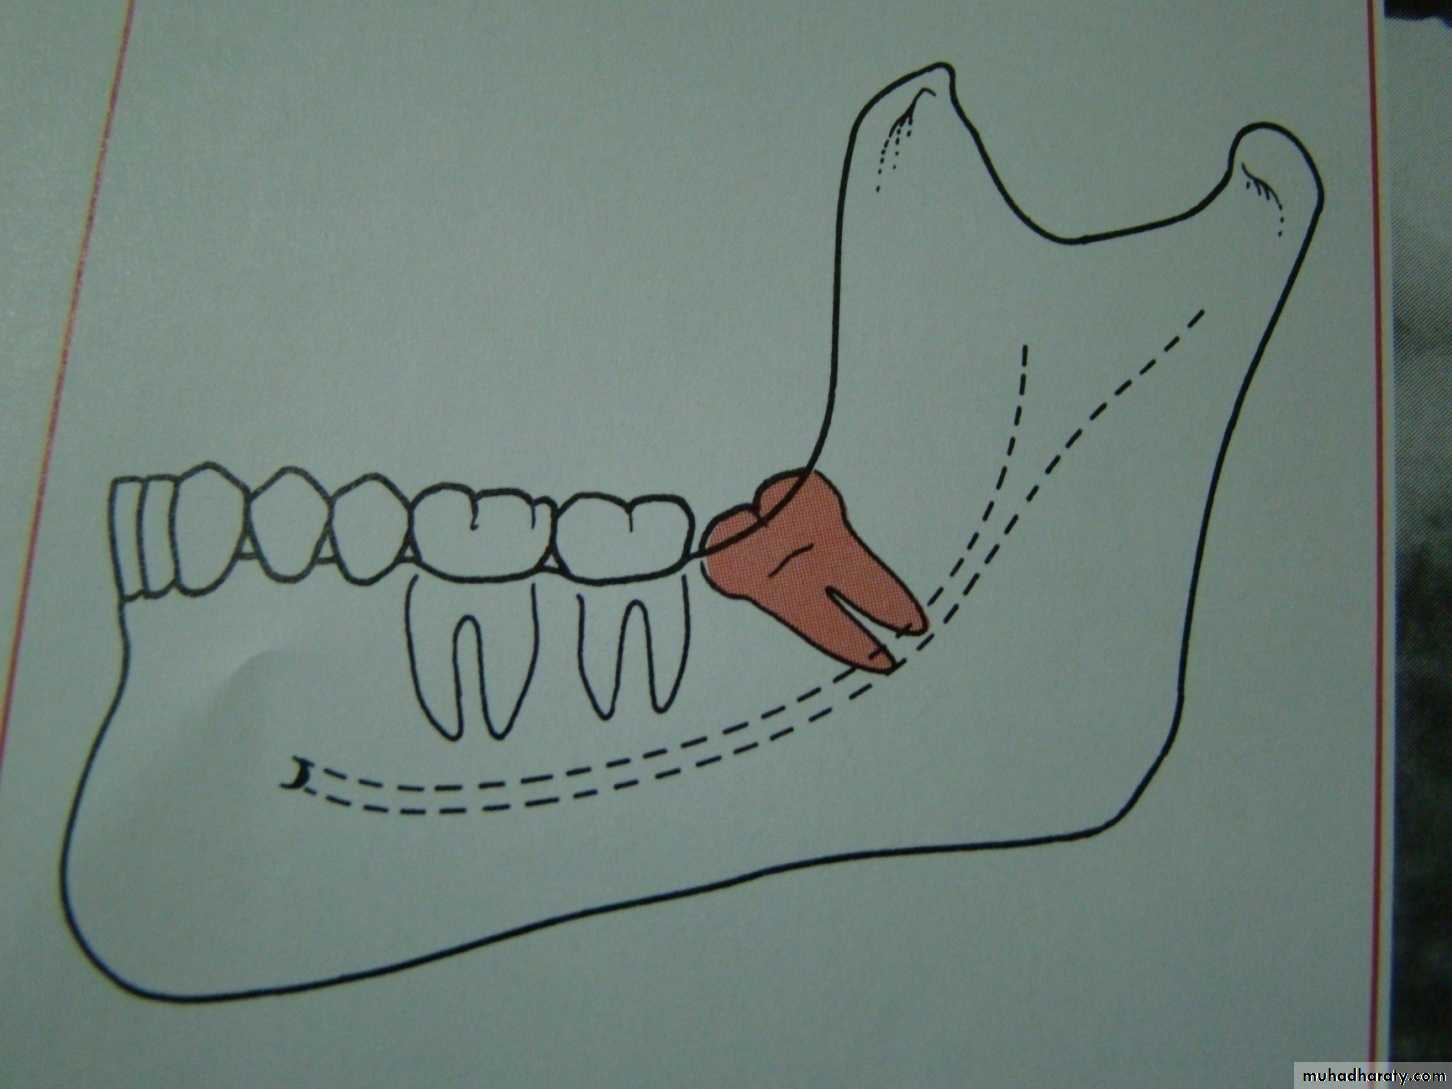

This is done to help the dentist in evaluation the extent and difficulty of the surgical procedureClassification of impacted lower third molar

1- Pell and Gregory classification according to the depth or according to the relation of the impacted tooth to the occlusal plane of the lower second molar2- Pell and Gregory classification according to the relation ship of the lower second molar to the anterior border of the ramus

3- Winters classification according to the angulations of the long axis of the impacted tooth

Relation of the impacted tooth to the anterior border of the ramus

Class 1 : the space between the lower second molar and the anterior border of the ramus is sufficient to accommodate the mesio distal dimension of the crown of the impacted lower third molarClass 2 : the space between the lower second molar and the ramus is insufficient to accommodate the crown of the impacted tooth .so part of it in the body and the other part lie in the ramus .

Class 3 the anterior border of the ramus lie near the distal surface of the lower second molar ,so ,the whole impacted tooth lie within the ramus .

Impacted tooth in relation to the ramus

Winters classification of impacted lower third molar

Mesio angularDisto angular

Horizontal

Vertical

Inverted

Transverse

Buccoversion

Linguversion